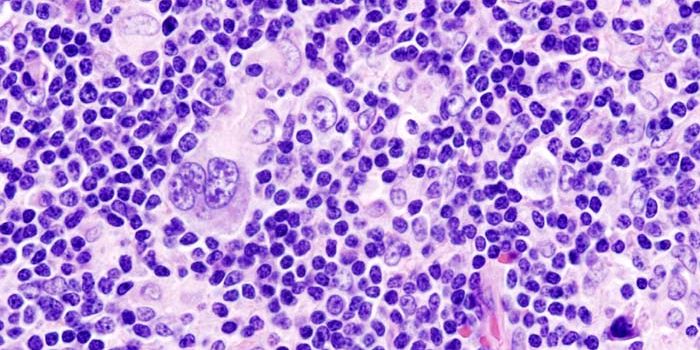

DEC 06, 2017ImmunologyA first-of-its-kind study reveals genetic variants in the immune system that increase the risk of Hodgkin lymphoma, a ty ...